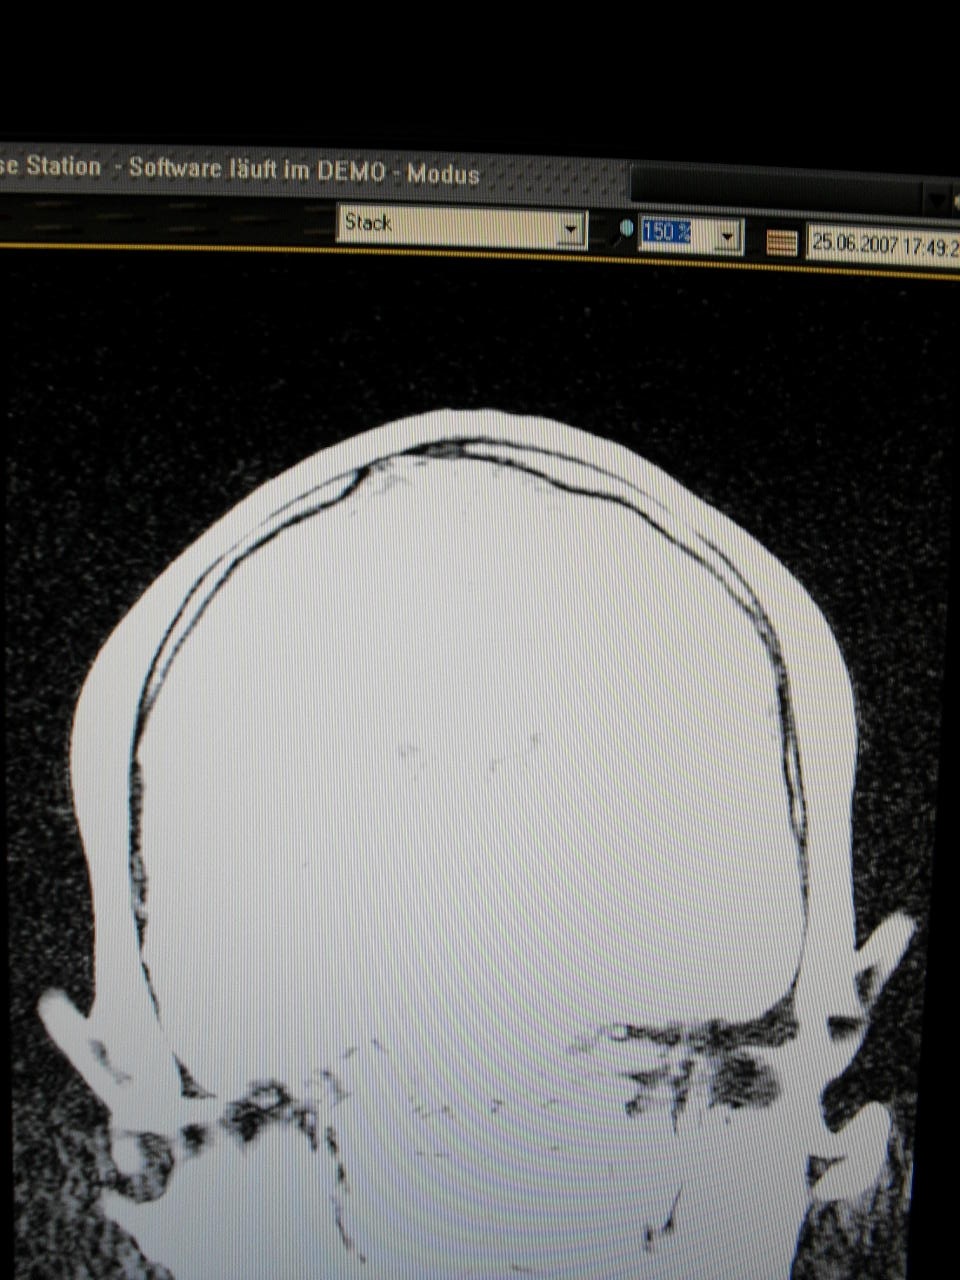

War auch schon paar mal in der Neurochirugie,weil ich probleme habe,da mir auf meiner Birne eine Knochenleiste nach oben heraus steht!

Jedenfalls bin ich mit meinen Nerven am Ende...und will euch mal paar Bilder von meinen MRT zeigen,weil ich der Meinung bin,das es dort diverse Auffälligkeiten nach meinen Standpunkt aus gibt!

Hier die Bilder...